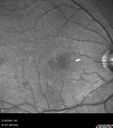

65 year old female Funny looking retinas referred by retina specialist Medical Hx: Hypertension, Systemic. Anxiety. Surgical Hx: Noncontributory. Systemic Meds: Amlodipine 5mg 1 tablet bid by mouth. Alprazolam, 0.5 mg oral tablet 1 tablet prn. buspirone hydrochloride 15 MG (as buspirone 13.7 MG) Oral Tablet 1 tablet bid. HCTZ 12.5 MG / Olmesartan medoxomil 20 MG Oral Tablet [Benicar HCT] 1 tablet qhs. VA 20/50 OU IOP 20 OU

Choroidal Melanocystosis85 views65 year old female with normal vision.00000